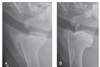

cranioproximal–craniodistal oblique view of the proximal portion of the humerus to diagnose long oblique fractures of the greater tubercle (Figure 98-1)

Figure 98-1. The position for obtaining a cranioproximal–craniodistal oblique view of the proximal portion of the humerus, which is best for imaging fractures of the greater tubercle.